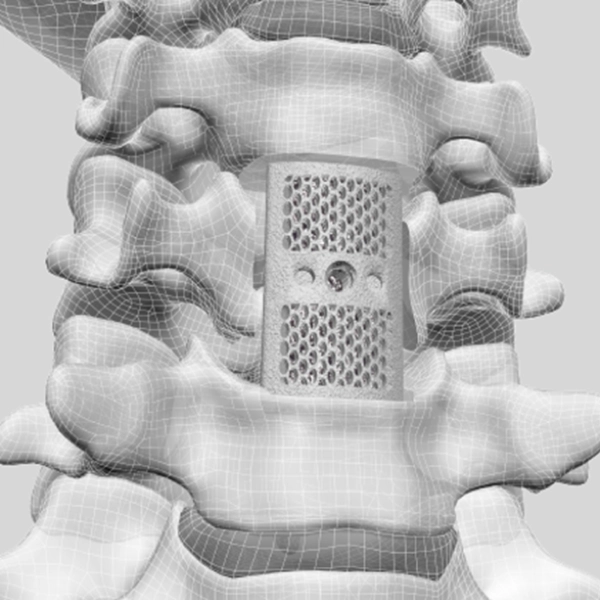

Corpectomy Cages

F3D Corpectomy